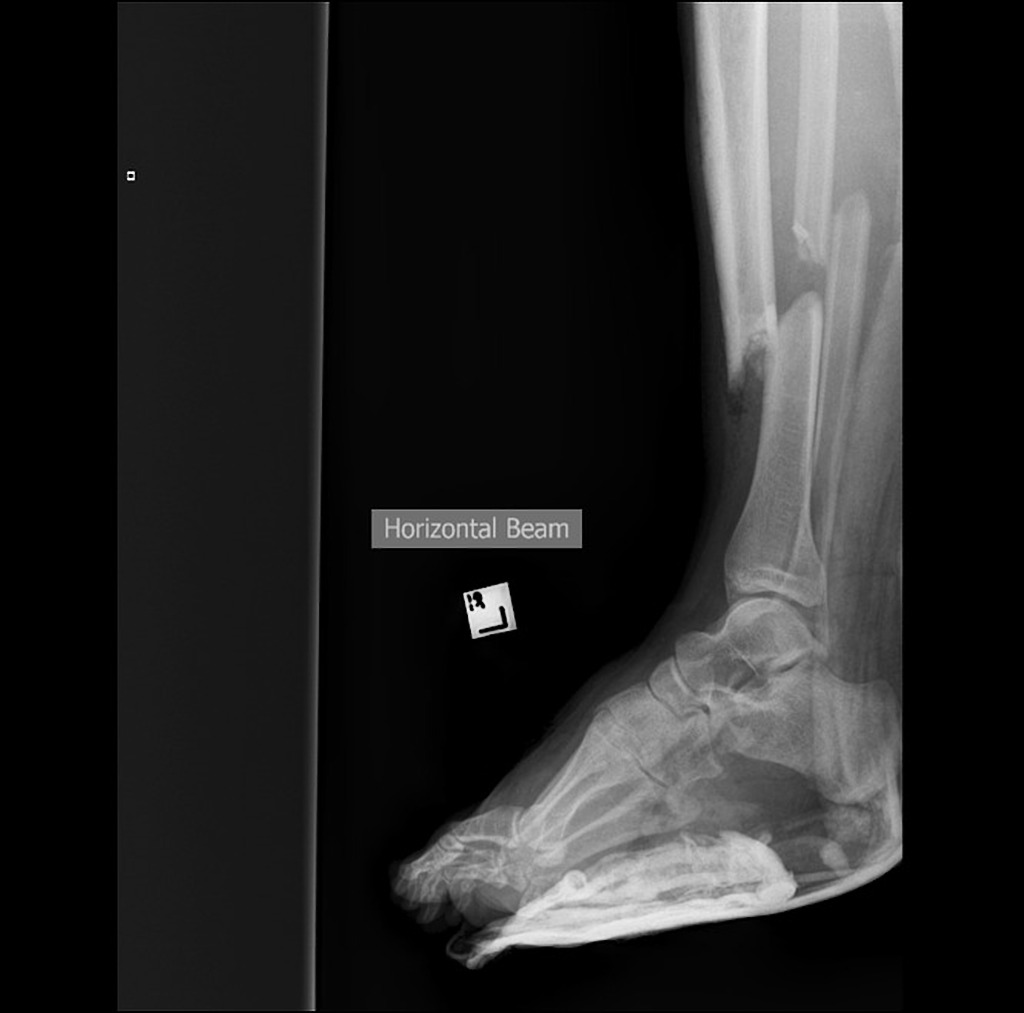

The story: he was doing well until he hit a bump, flew in the air and his shin collided with a metal pole that was poking out of the ground. They estimate he was going about 45 km/hr when he hit. He did not hit his head and was able to stand on one leg… although the other leg is “munted” as we say in Oz.

So – here we are. We work about 1000 miles from the closest Orthopaedic services. This guy has a wound with bone and marrow on view. The wound is filled with sand and little bits of debris from the beach. As you are drawing up the ketamine to facilitate further inspection and immobilisation you are imagining the long days he will spend in a hospital somewhere fighting off infection, hoping his bones will heal and that the skin will survive. This is a nasty injury- one that could result in serious disability. Click here for more information on disability and benefits you can get from it.

I think that’s actually a Gustilo 3A – the degree of displacement suggests that it’s more than a 2.

The images are of course factitious – sorry I couldn’t get a good Gustilo II!